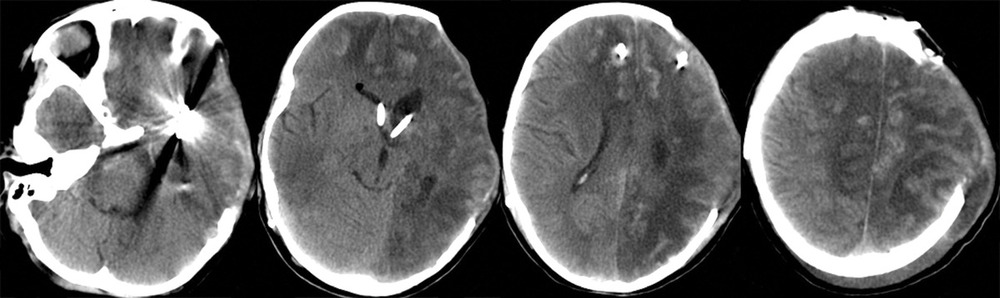

При поступлении на 2-е сутки после аСАК девочка находилась в коматозном состоянии: 4 балла по шкале комы Глазго. При неврологическом осмотре выявлялись мидриаз (D=S) и отсутствие фотореакции. В ответ на болевой стимул отмечались реакции по типу децеребрации. По данным компьютерной томографии (КТ) и КТ-ангиографии головного мозга были выявлены: аневризма левой СМА, субарахноидально-паренхиматозное кровоизлияние с формированием гематомы объемом около 30 см3 в области левой сильвиевой щели, латеральная дислокация срединных структур 6,5 мм, сдавление охватывающей цистерны (рис. 1).

После экстренно проведенной коррекции ВЧГ (седация пропофолом, гиперосмолярная терапия, гипервентиляция) наблюдалась положительная динамика неврологической симптоматики в виде сужения зрачков и появления фотореакции с обеих сторон. В дальнейшем параметры искусственной вентиляции легких (ИВЛ) были подобраны так, чтобы обеспечить нормовентиляцию: PaCO2 в переделах 35—45 мм рт. ст. и PaO2 в пределах 100—110 мм рт. ст. Был начат инвазивный мониторинг артериального давления (АД), при этом системное АД без вазопрессорной поддержки составляло 100/60—110/70 мм рт.ст., ЧСС — 77—90 уд/мин. В связи с клинико-рентгенологической картиной отека мозга и дислокацией срединных структур мозга, согласно КТ, коматозным состоянием пациентки и наличием реакции на экстренные терапевтические манипуляции было принято решение об экстренном выполнении нейрохирургической операции. В течение полутора часов после поступления ребенка было выполнено нейрохирургическое вмешательство: клипирование аневризмы бифуркации левой СМА, удаление внутримозговой гематомы левой височной доли, наружная декомпрессия черепа слева. Операция была завершена установкой паренхиматозного датчика фирмы Codman в левую премоторную область для мониторинга внутричерепного давления (ВЧД) и контроля церебрального перфузионного давления (ЦПД). ВЧД при установке датчика составило 2 мм рт.ст. На следующий день после операции выполнена контрольная КТ головного мозга, по данным которой диффузный отек сохранялся (рис. 2).